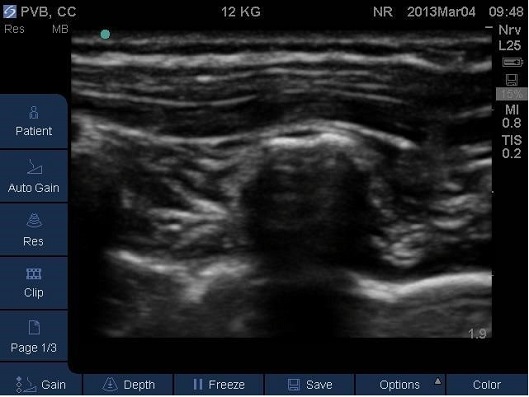

- Correct placement of the needle in the thoracic Paravertebral space should be confirmed by the anterior displacement of pleural upon injection of a small bolus of saline or local anaesthetic (Fig 13-16).

- Once confirmed the required volume of local anaesthetic should be injected.

Fig 15. Paravertebral space entered by needle, pleura displaced anteriorly by local anaesthetic. TP –transverse process. Local anaesthetic spread marked in light blue